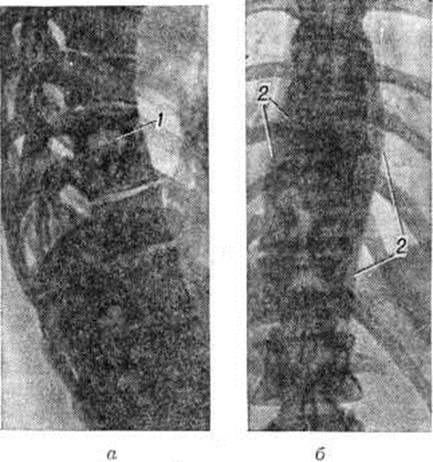

Во многих случаях при туберкулёзном Спондилит натечные абсцессы могут быть диагностированы рентгенологически. В шейном отделе позвоночника абсцесс распознается по дугообразному выпячиванию задней стенки трахеи и глотки. В грудном отделе тень абсцесса на фоне лёгочных полей довольно отчётливо дифференцируется и имеет форму веретена, луковицы и так далее Очертания абсцесса гладкие и чёткие (рисунок 5). Для уточнения объёма и распространённости абсцесса применяют абсцессографию (рентгенологические исследование после заполнения опорожненной полости абсцесса контрастным веществом), а при наличии свища — фистулографию (смотри полный свод знаний). В поясничном отделе абсцессы диагностируются по косвенным признакам — выпячиванию наружного края большой поясничной мышцы.

По мере затихания и последующей стабилизации туберкулёзного процесса натечный абсцесс может рассосаться или обызвествиться. Обызвествленные участки имеют вид мелких или крупных конгломератов (рисунок 6). Рентгенологические признаками затихания туберкулёзного Спондилит являются: уменьшение размеров абсцесса, увеличение его плотности или обызвествление; стабильность рентгенологическое признаков без появления новых деструктивных изменений, четкая отграниченность каверн; окостенение фиброзных колец и продольных связок позвоночника в виде скобок и краевых разрастаний; костное спаяние (анкилозирование) дуг и суставных отростков позвонков.